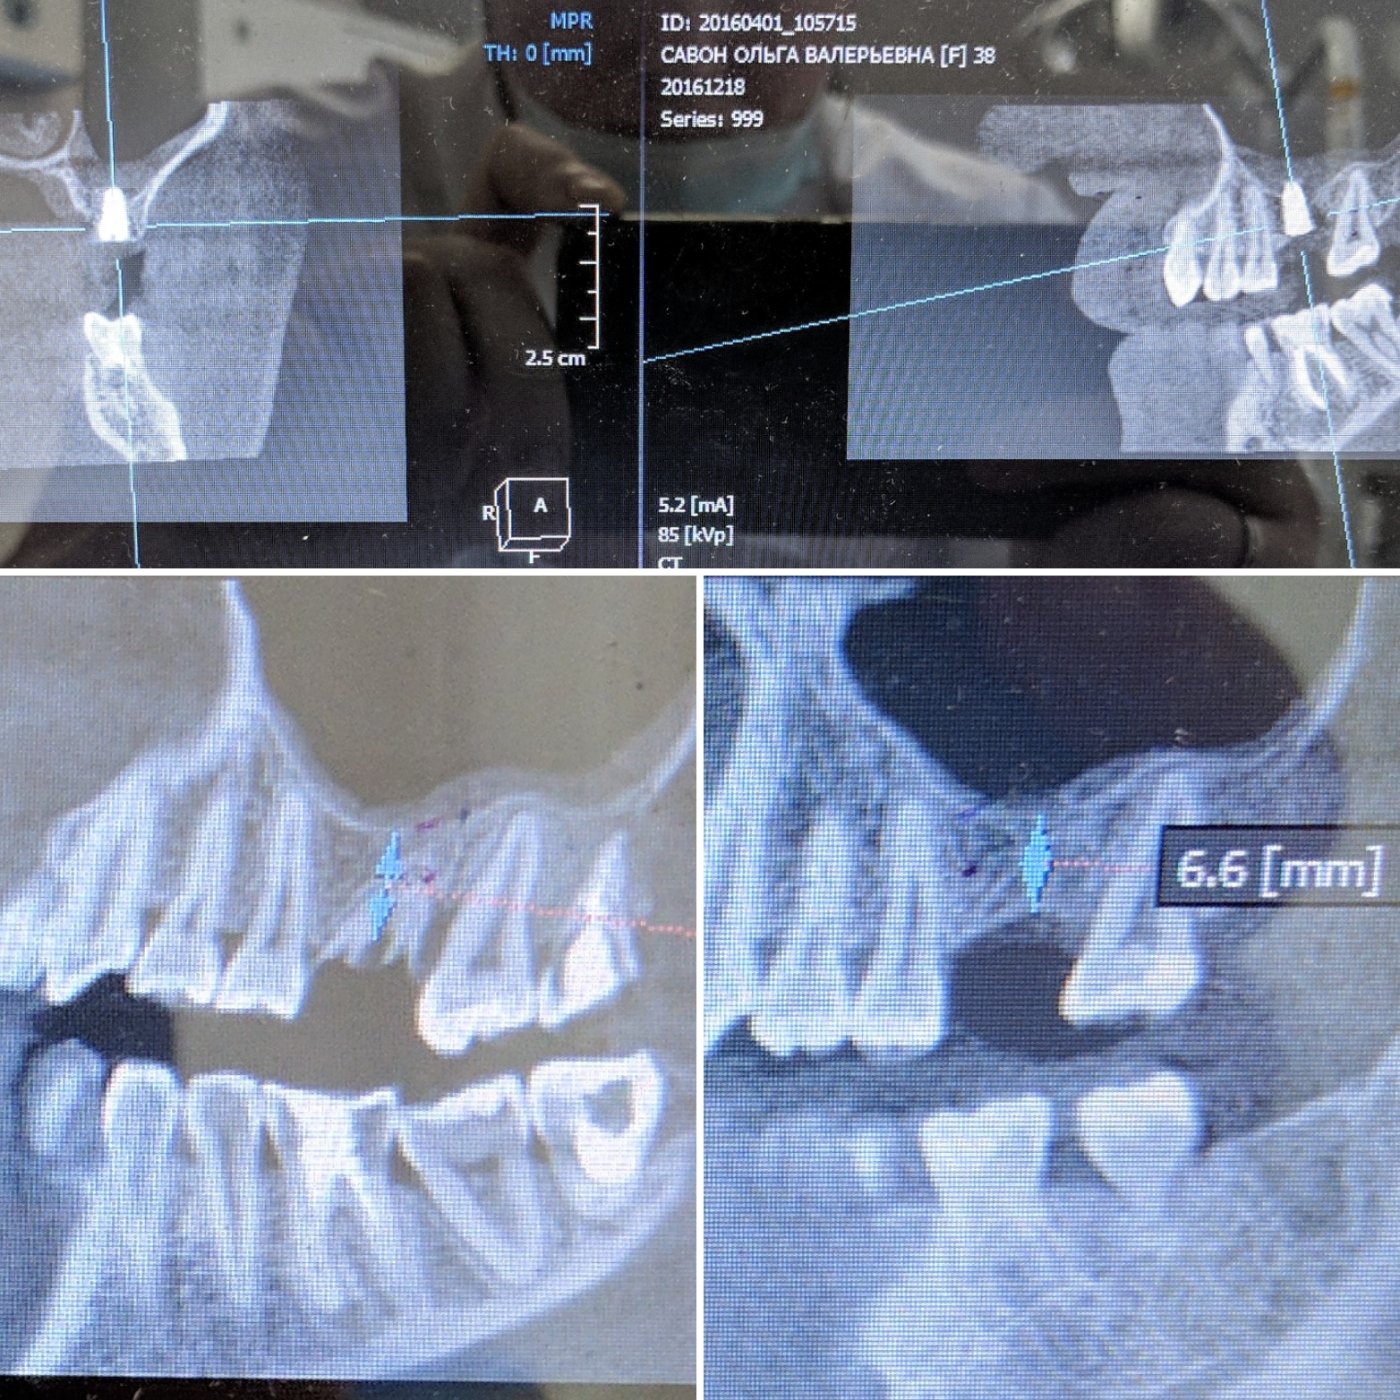

Из навыков: открытый и закрытый синус лифтинг, одномоментная имплантация , расщепление альвеолярного гребня, sausage technique и другая направленная костная регенирация, опыт в работе с титановыми сетками на имплантатах Osstem система Smart Builder, мягкотканная пластика десны, пародонтологические операции. Удаление зубов любой сложности, чтение клкт (3D) и составления рационального плана лечения, стремление расти и развиваться профессионально!

Учился и работал в г. Омске, а в 2017г. переехал с семьёй в г. Белгород. На данный момент работаю в клинике частной Дента Л плюс г. Белгород.